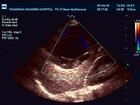

肝包蟲病傳染示意圖(1)為首選檢查方法。囊腫呈圓形成類圓形,壁較厚,邊界清楚、光整,囊內可見子囊,其中可見光環、光團或活動光點。

(2)病變周圍可有回聲增強。

⑵肝超音波檢查:B型超聲斷層檢查,囊型包蟲顯示邊界明確的液性暗區,其內所見光點或小光團為子囊;泡型包蟲則顯示密集光點,並見大小不等的光團,底光帶多不清晰。